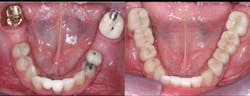

A: Full-zirconia restorations have been available for the past years or so. They have evolved from relatively unesthetic, opaque crowns and bridges to significantly improved restorations with acceptable esthetics (figures 1 and 2). Most dentists have noted that the majority of zirconia restorations are lighter in color than they requested on their lab order. The intense opacity of this material makes the restorations appear light in color. As the new generation of "esthetic zirconia" restorations continues to improve, this color problem will probably be overcome.

Figure 1: These full-zirconia fixed prostheses have served in the mouth for three years. Clinicians Report Foundation has research (TRAC Division) on zirconia-based three-unit fixed prostheses now serving for nearly 12 years.